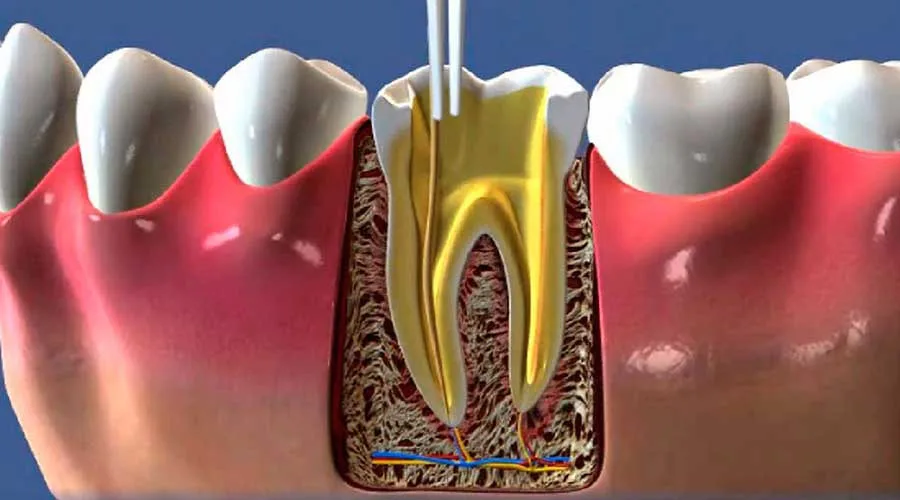

O consultório endodontia oferece uma série de benefícios cruciais para a longevidade da saúde dental. Este espaço é especializado em tratar problemas que afetam a polpa dentária, sendo a solução definitiva para quem sofre com dores intensas e quadros infecciosos.

Além de cessar o desconforto, o tratamento endodôntico foca na preservação do dente natural. Manter o elemento original é fundamental para a integridade da arcada e para o equilíbrio das funções mastigatórias no cotidiano.

Buscar o suporte de um consultório endodontia permite que o paciente elimine focos bacterianos de forma precisa. Através de técnicas modernas, a saúde bucal geral é aprimorada, estabelecendo um ambiente biológico muito mais saudável e protegido.

O tratamento endodôntico contribui para uma mastigação mais eficiente e segura. Ao salvar o dente, o especialista assegura que as forças oclusais permaneçam distribuídas, prevenindo desgastes irregulares e problemas na articulação da mandíbula.

Tecnologia de Precisão: Uso de microscopia operatória e localizadores apicais para maior exatidão;

O uso de equipamentos modernos resulta em intervenções menos invasivas e diagnósticos milimétricos. Na unidade técnica, o atendimento personalizado é prioridade, permitindo que todas as preocupações do paciente sejam acolhidas adequadamente.

Sessão de Tratamento: Procedimento realizado sob anestesia local eficaz, priorizando o bem-estar;